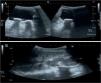

Se realizan una radiografía simple de abdomen y una ecografía abdominal, donde se aprecian litiasis renovesicales, nefromegalia izquierda e imágenes sugestivas de pionefrosis (figs. 1 y 2).

A) Focos cálcicos con sombra acústica posterior indicativos de litiasis vesicales. B) Nefromegalia izquierda y dilatación pielocalicial con contenido espeso ecogénico indicativo de pionefrosis. Pobre diferenciación corticomedular y focos cálcicos con sombra posterior en pelvis renal izquierda.